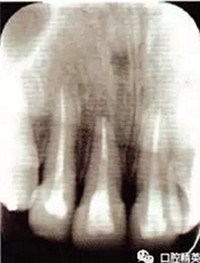

2冠根折,唇側(cè)斷端至齦下2mm,露髓,叩痛(+),不松,齦緣滲血;1冠折,未露髓,部分脫出,叩痛(+),松Ⅲ度,近中齦乳頭撕裂,長約1.5 cm;1挫入,切斷折斷,位于拉冠中部,叩診高調(diào)金屬音,不松,近中齦乳頭撕裂,長約1.5 cm;2見釉質(zhì)裂紋,叩痛(+),不松,齦緣滲血(圖1);以上牙齒X線均未見明顯根折線(圖2)。

圖2外傷牙鋼絲+釉質(zhì)粘接劑固定術(shù)后根尖片